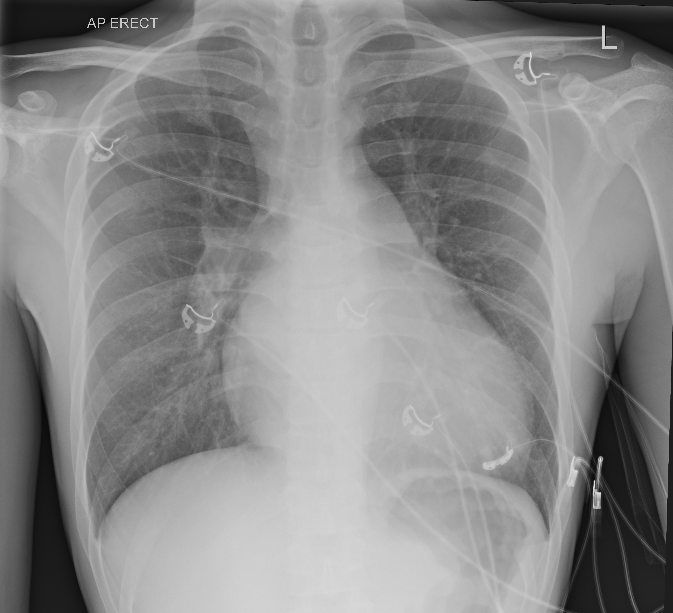

• CXR is notable for an enlarged cardiac silhouette which is clearly abnormal in this young patient. Lung fields are largely clear, but there is some prominent upper lobe vasculature seen bilaterally. Costophrenic angles are clear.